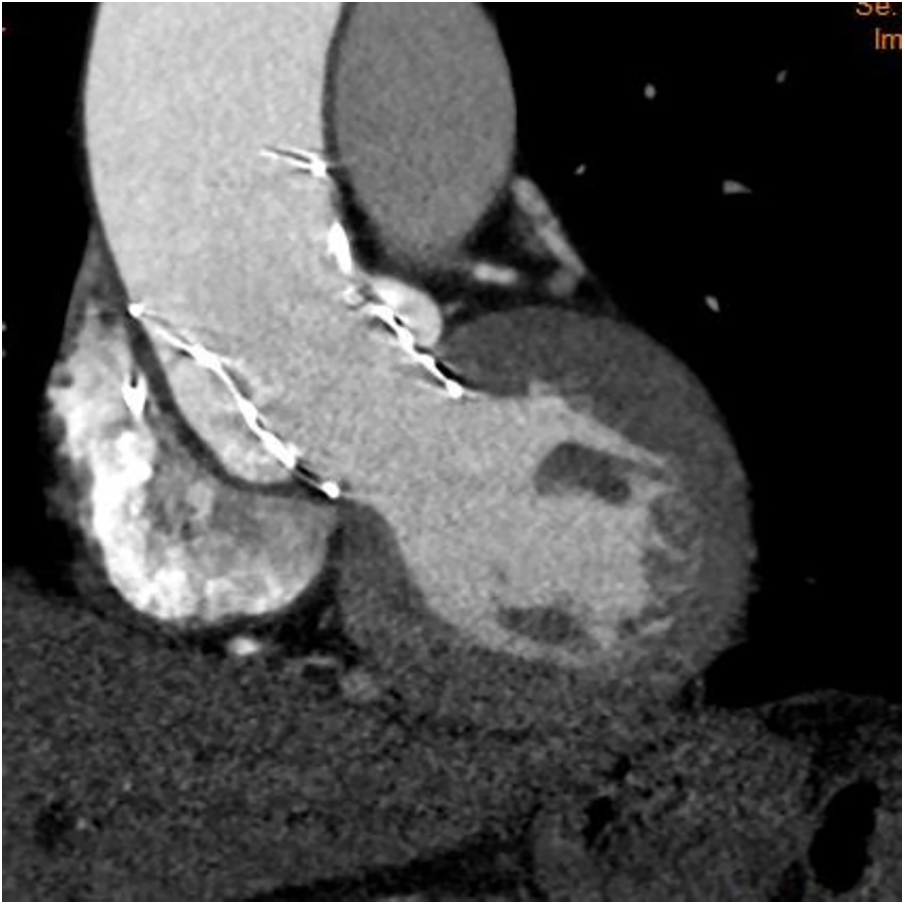

Figure 3

The follow-up computed tomography showing a will-positioned THV.

Therefore, we decided to pre-place a snare. The snare system, with a loop diameter of 20 mm and a 90° angle, was employed. A 4-F sheath was advanced through the ipsilateral femoral artery, with the prosthesis captured at the level of the descending aorta. The snare captured the distal fifth of the delivery capsule. During the second deployment, we used an unconventional approach by continuously pulling the prosthesis during deployment to enhance coaxiality until it reached the stable position. This led to a more optimal implantation depth below the left coronary sinus (Figures 2B–D). After the TTE assessment, no apparent perivalvular leak was observed, and there was no impact on the anterior leaflet motion of the mitral valve. We withdrew the snare catheter and released the prosthesis completely under rapid pacing at 120 beats/min to ensure valve stability. Upon a follow-up TTE before discharge, the LVEDd had decreased to 56 mm, and no residual AR was observed. The CT scan confirmed proper positioning and normal function of the THV (Figure 3).